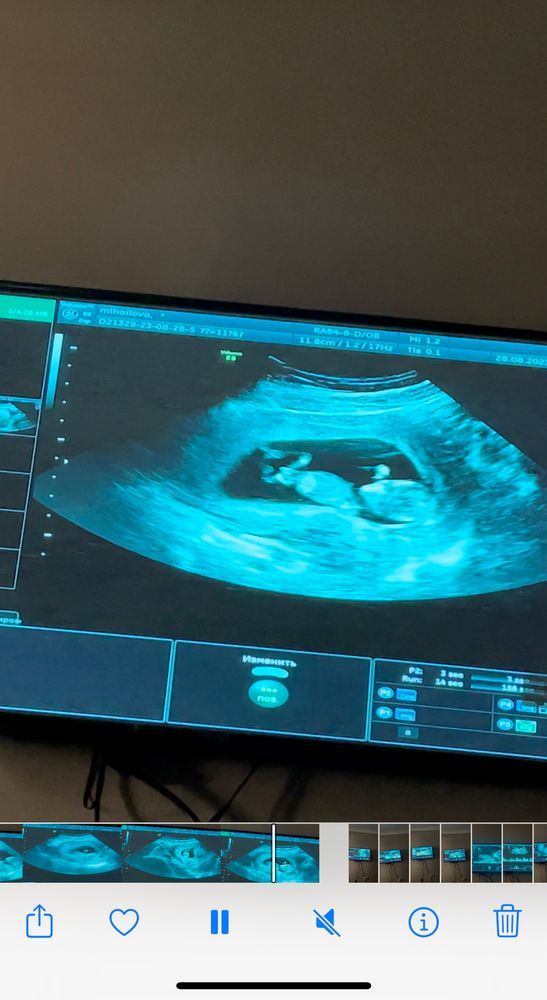

Кто расшифрует показатели по скринингу и пол малыша?🙈 Была сегодня на скрининге 🥹 срок по узи и месячным день в день. Пол сказала узистка даже смотреть не будет, как я не просила, сказала она мне терпеть 🥲 отправлю замерчики😁 правда они на укр языке. Посмотрите знающим глазом 😁🫂 и может кто по фото поймёт пол малыша, интерес берет своё

Генриетта , а вот здесь можно посмотреть по половому бугорку, тут у вас тоже похоже на девочку.

Евгения, прикол 🙈 я думала мальчик хахахах но это видимо пупок там 🤣🤣🤣

но там вообще крошечное всё 🙈